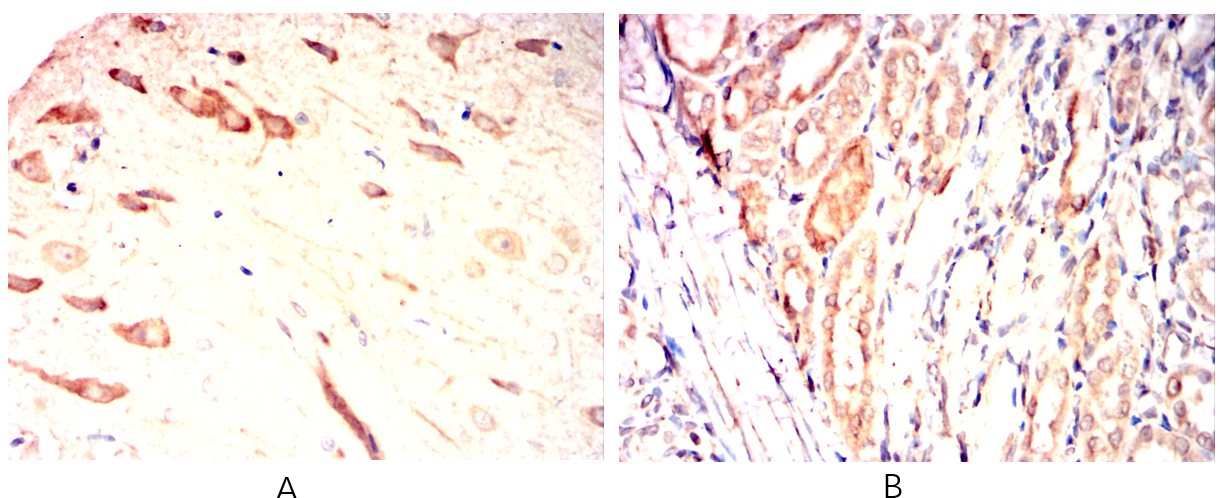

Immunohistochemical analysis of paraffin-embedded Rat brain(A)Rat kidney(B) using BDH1 mouse mAb with DAB staining